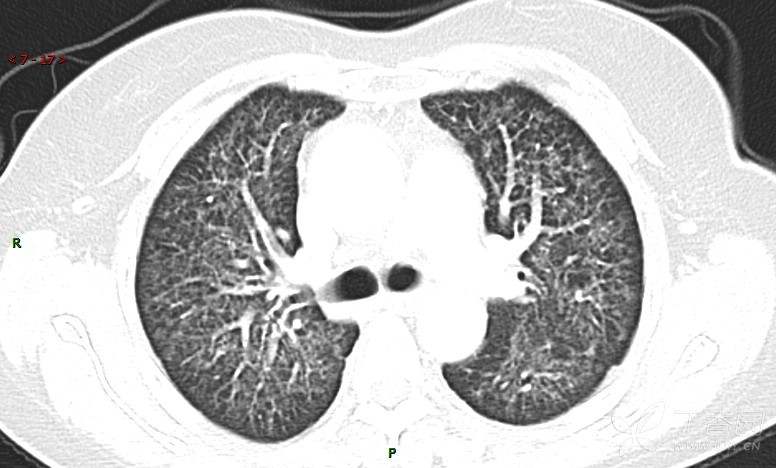

肺内弥漫性网状结节影,PET-CT却无阳性病灶,这是?(附其他2例链接)

女性,58岁,阵发性咳嗽2月,加重1月。

患者于2月前无明显诱因出现咳嗽,以阵发性干咳为主,接触冷空气后咳嗽明显,偶咳少量白色泡沫样痰,咳嗽剧烈时感憋喘,无发热、盗汗,无头痛、头晕,无胸痛、咯血,无恶心、呕吐,无腹痛、腹泻,无尿频、尿痛等不适,于当地医院给予肌注及静脉药物治疗,具体药物名称不详,效果欠佳,近1月来患者咳嗽频率较前增加,咳嗽剧烈时感双侧季肋区疼痛不适,10余天前出现发热,体温在38℃左右,伴畏寒、寒战,无头痛、头晕,无纳差、乏力等不适,药物治疗后体温降至正常,仍阵发性咳嗽,今为求进一步诊治,就诊于我院急诊,因呼吸内科暂无床位,急诊门诊以“肺间质病变”收入急诊留观室,给予“抗感染、止咳”等对症支持治疗后,今日以“肺间质性病变”收入我科,患者自本次发病以来,神志清,精神可,饮食尚可,睡眠一般,大小便正常,体重较前无明显变化。

患者活检肺组织后行PET/CT检查